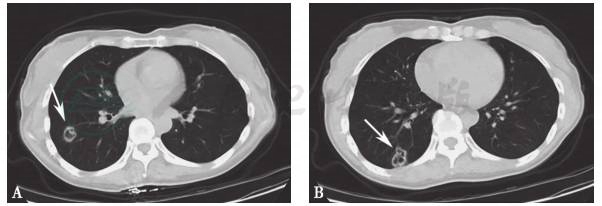

胸部CT提示“右中肺机化性肺炎较前加重”(图3);肌电图大致正常。

图3 2011年3月8日CT示右中肺机化性肺炎较前加重